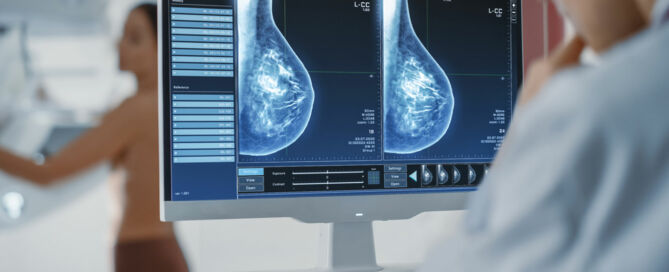

Quality control in mammography: 6 practical tips

The aim of quality control in mammography is to maximize the benefits of exams while minimizing their potential risks. By law, mammogram screening programs must include quality control measures. In fact, ongoing internal quality controls provide a sound foundation for clinics to pass external reviews, such as audits and certifications, with flying colors. So, how can clinics maintain consistently high standards in mammography, and how can innovative technology such as artificial intelligence (AI) help? In this blog, we’ll provide a helpful overview with six practical tips on how to achieve this.